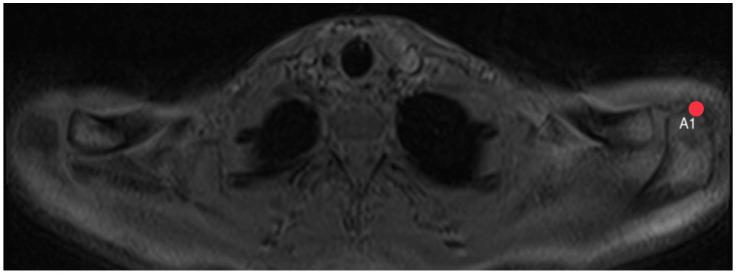

Shoulder pain is a common issue often linked to conditions such as subacromial impingement or rotator cuff lesions. The role of the acromion in these symptoms remains a subject of debate. This study aims to establish standardized values for commonly used acromion dimensions based on whole-body MRI scans of a large and healthy population and to investigate potential correlations between acromion shape and influencing factors such as sex, age, BMI, dominant hand, and shoulder pain. The study used whole-body MRI scans from the Study of Health in Pomerania, a German population-based study. Acromion index, acromion tilt, and acromion slope were measured. Interrater variability was tested with two independent, trained viewers on 100 MRI sequences before actual measurements started. Descriptive statistics and logistic regression were used to evaluate the results. We could define reference values based on a shoulder-healthy population for each acromion parameter within the 2.5 to 97.5 percentile. No significant differences were found in acromion slope, tilt, and index between male and female participants. No significant correlations were observed between acromion morphology and anthropometric parameters such as height, weight, or BMI. No significant differences were observed in acromion parameters between dominant and non-dominant hands or stated pain intensity. This study provides valuable reference values for acromion-related parameters, offering insight into the anatomy of a healthy shoulder. The findings indicate no significant differences in acromion morphology based on sex, weight, BMI, or dominant hand. Further research is necessary to ascertain the clinical implications of these reference values. The establishment of standardized reference values opens new possibilities for enhancing clinical decision making regarding surgical interventions, such as acromioplasty.

肩部疼痛是一个常见问题,通常与肩峰下撞击或肩袖损伤等病症有关。肩峰在这些症状中所起的作用仍是一个有争议的话题。本研究旨在基于对大量健康人群的全身MRI扫描,建立常用肩峰尺寸的标准化值,并研究肩峰形状与性别、年龄、体重指数、优势手和肩部疼痛等影响因素之间的潜在相关性。该研究使用了来自德国基于人群的波美拉尼亚健康研究的全身MRI扫描数据。测量了肩峰指数、肩峰倾斜度和肩峰斜率。在实际测量开始前,由两名独立的、经过培训的观察者对100个MRI序列进行了观察者间变异性测试。使用描述性统计和逻辑回归来评估结果。我们可以根据肩部健康人群为每个肩峰参数在第2.5至97.5百分位数内定义参考值。在男性和女性参与者之间,肩峰斜率、倾斜度和指数没有发现显著差异。在肩峰形态与身高、体重或体重指数等人体测量参数之间未观察到显著相关性。在优势手和非优势手之间或所述疼痛强度方面,肩峰参数没有观察到显著差异。本研究为与肩峰相关的参数提供了有价值的参考值,有助于深入了解健康肩部的解剖结构。研究结果表明,基于性别、体重、体重指数或优势手,肩峰形态没有显著差异。有必要进行进一步研究以确定这些参考值的临床意义。标准化参考值的建立为加强关于手术干预(如肩峰成形术)的临床决策开辟了新的可能性。